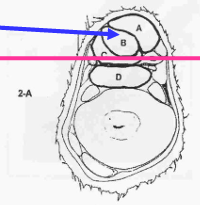

¿De qué zona es este corte? y ¿cuáles son las estrucutras que se ven?

Zona 1B

A - Tendón flexor digital superficial (TFDS)

B - Tendón flexor digital profundo (TFDP)

C - Ligamento frenador (Check Ligament)

D - Ligamento suspensorio del menudillo (LSM)